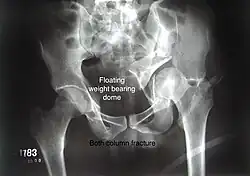

Both column fracture showing floating weight bearing dome -

Combined both column fractures | These are the most complex injuries. Here the weight bearing roof or dome of the acetabulum is a floating piece. This adds to complexity of management.

All three x-ray views plus CT scan is a must for diagnosis and management of this complex injury.

Like any other acetabular fracture, if the femoral head is dislocated out of the socket, early reduction into socket is a priority. However, in this injury, non-operative treatment rarely gives satisfactory results. Surgical management is ideal. The choice of approach rests with the surgeon, but going from front, or anterior approach is must. The posterior injury may be tacked with anterior approach by experienced surgeon. If the patient is unfit to undergo major surgery due to any reason, longitudinal traction to achieve secondary congruence of hip may help to restore hip function, though partially. |